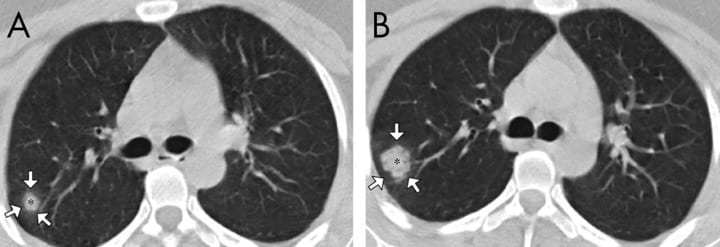

طبق یک مطالعه موردی، یک زن ۳۳ ساله با تب و سرفه پنج روزه، دمای بدن ۳۸.۸ درجه، مشکل تنفسی و تعداد پایین گلبولهای سفید خون، نشانهای از عفونت، به بیمارستانی در لانژو چین مراجعه کرد.در سی تی اسکن اولیه، محققان بیمارستان دانشگاه لانژو «کدورت شیشه مات» را در گوشه پایین ریههای وی شناسایی کردند.به این بیمار اینترفرون، پروتئینی برای درمان عفونتهای ویروسی، تجویز شد اما سه روز بعد (و بعد از درمان او) علائم بارزتر شدند. همین اتفاق در بیماران SARS نیز رخ داده است. «اگر از این شیوع اطلاع نداشتیم با مشاهده اسکن تشخیص پنومونی میدادیم، زیرا این شایع ترین چیزی است که میبینیم.»«ذات الریه معمولاً به سرعت پیشرفت نمیکند»، بنابراین این مورد منتفی است.اسکن ریه کرونایی یک خانم ۲۷ ساله که در ووهان کار میکرد، یک «هاله شیشه مات» را نشان داد؛ لکههای سفیدی که ندول کوچکی را احاطه کردهاند.

مطالعه دیگر در مورد بیمارانی که از ویروس کرونا بهبود یافتند، پیشنهاد کرد که این الگو بین بیماران نوع خفیفتر شایع است. تقریباً شبیه یک جاده سنگفرش است. گاهی اوقات کل ریه را می پوشاند اما دیدن آن در چند منطقه کوچک ناشایع و کمی غیرمعمول است.مطالعه دیگر در مورد بیمارانی که از ویروس کرونا بهبود یافتند، پیشنهاد کرد که این الگو بین بیماران نوع خفیفتر شایع است. تقریباً شبیه یک جاده سنگفرش است. گاهی اوقات کل ریه را می پوشاند اما دیدن آن در چند منطقه کوچک ناشایع و کمی غیرمعمول است.مطالعهای که روی ۲۱ بیمار در سه استان چین انجام شد، چهار بیمار را با اسکن «الگوی انتشار پیشرونده» نشان داد. «تقریباً شبیه یک جاده سنگفرش است. گاهی اوقات کل ریه را می پوشاند اما دیدن آن در چند منطقه کوچک ناشایع و کمی غیرمعمول است.»وی گفت که این الگو در برخی از اسکن های SARS و MERS نیز دیده شده است. مطالعه دیگر در مورد بیمارانی که از ویروس کرونا بهبود یافتند، پیشنهاد کرد که این الگو بین بیماران نوع خفیفتر شایع است.یک مطالعه در شانگهای الگویی شبکه مانند به نام «رتیکولاسیون» را شناسایی کرد که در اسکن یک پیرمرد ۷۵ ساله مشاهده شده بود.محققان مرکز بالینی بهداشت عمومی شانگهای، اسکن این بیمار را سه روز پس از بستری شدن مرد در بیمارستان، مورد تجزیه و تحلیل قرار دادند. علاوه بر «کدورت شیشه مات» الگوی شبکه مانند «رتیکولاسون» نیز دیده شد که نشانگر آسیب ریه و معمولاً با سندرم زجر تنفسی حاد (ARDS) همراه است.مطالعه اخیر در The Lancet نشان داد که ویروس کرونا میتواند منجر به ARDS شود که اغلب کشنده است.به گفته محققان شانگهای، ۲۲ درصد از ۵۰ بیماری که آنها بررسی کردند، در اسکن خود الگوی رتیکولاسون و حدود ۷۷٪ «کدورت شیشه مات» را نشان دادند، در حالی که تقریبا ۶۰٪ دارای کانسولیدیشن بودند؛ بافت ریه که به جای هوا با مایع پر میشود.محققان شانگهای در نهایت به این نتیجه رسیدند که برای تشخیص کرونا به سه جزء نیاز است: تب یا سرفه، وجود کدورت شیشه مات در هر دو ریه و سابقه قرار گرفتن در معرض ویروس.اما ویروس کرونا همیشه بلافاصله در اسکن ظاهر نمیشود.مایکل چونگ، نویسنده اصلی مطالعه لانژو، در تاریخ ۳ فوریه گفت: «ما برای رد قطعی حضور ویروس نمیتوانیم به CT متکی باشیم.»